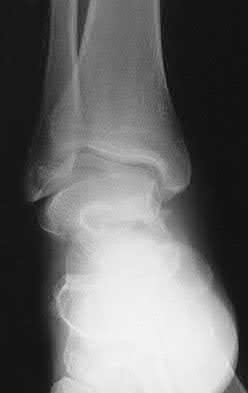

Figure A is an AP radiograph of a posterior knee dislocation. Figure B is a lateral showing the same injury.